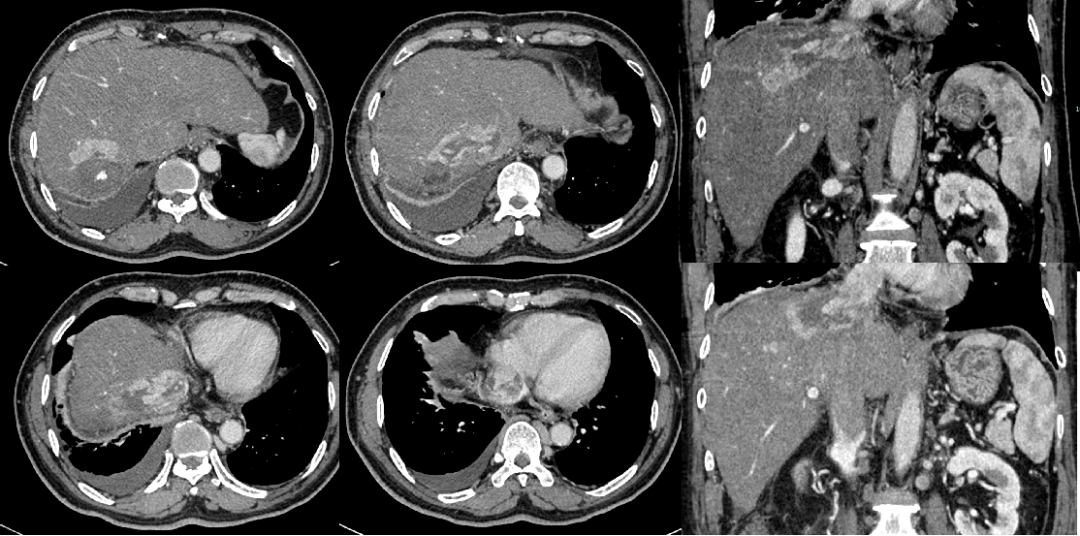

2018年4月8日复查CT示,肝S7病灶未见强化,病灶周边肝实质较明显强化,病灶周围见片状低密度影,增强扫描见不均匀明显强化。肿块侵犯肝静脉、下腔静脉、右心房(图4)。

2018年4月10日行TACE治疗,出院后口服阿帕替尼500 mg治疗。

2018年5月23日复查CT,提示肝脏S7段病灶内见少量碘油沉积,未见明显强化;肝右静脉、下腔静脉及右心房内病变较前缩小,见少量碘油沉积,增强扫描大部分无明显强化。评价为PR(图5)。